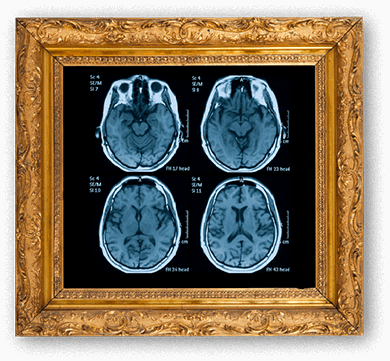

Your brain in a frame for display mb-3

Financial compensation is offered, plus you get a high-quality picture of your brain to frame and display!